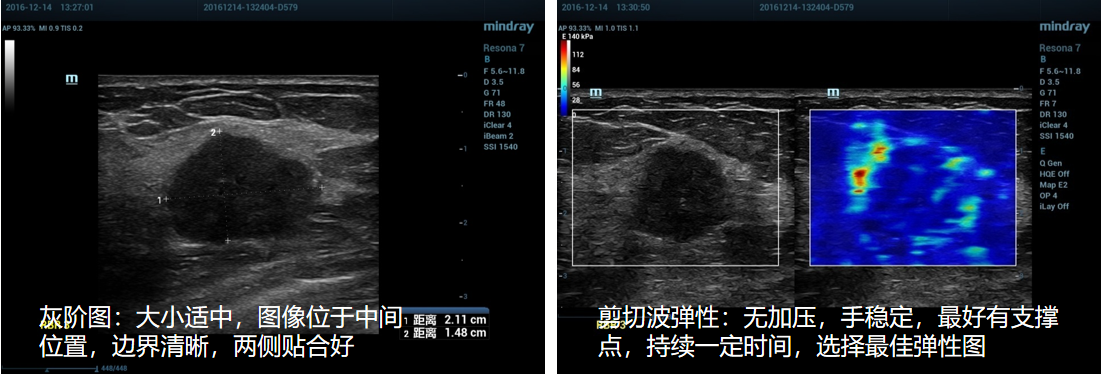

②探头:探头垂直皮肤,勿施加压力,启动弹性成像。

③ROI框大小:取样框需要包含肿块、正常腺体、脂肪组织。

④ROI框位置:将肿块置于弹性成像感兴趣区中心位置。

4、正确操作示范:

①乳腺剪切波弹性成像